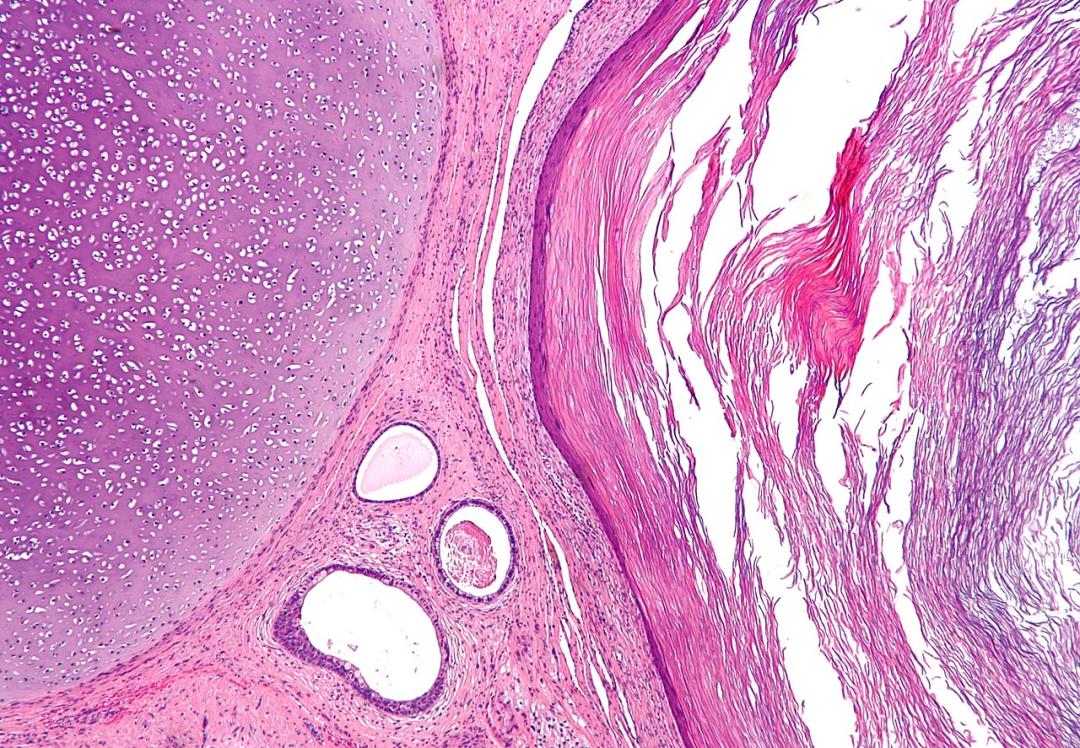

畸胎瘤的显微照片,这是一种典型的具有三胚层的组织的肿瘤。图像显示中胚层(未成熟软骨-图像左上角)、内胚层(胃肠腺-图像中心底部)和外胚层(表皮-图像右侧)衍生的组织。图片来源:wikipedia前寒武纪末除了已灭绝的“文德类”动物,常见的辐射对称动物是海绵动物、刺胞动物,还有无法归入已知动物门类的灭绝动物。它们虽然都是多细胞动物,但它们只发育了外胚层和内胚层,都缺乏中胚层,因而无法形成真皮、体腔膜及系膜等,因此也没有现代动物所具有的嘴、骨骼,更缺乏动物通常具有的运动、取食和消化等功能器官。因此,呈辐射对称造型的动物一般都是营固着底栖生活或漂浮生活。